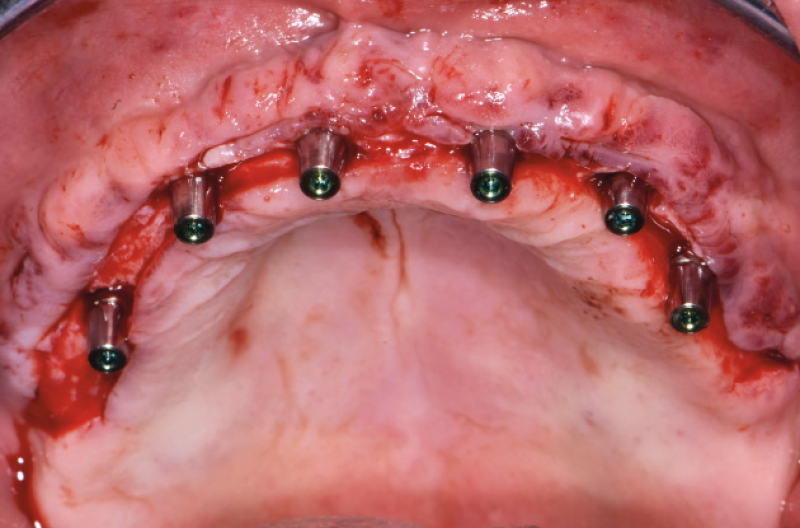

Ho riaperto il mascellare superiore con un lembo a spessore parziale palatino e con scarichi solo distali per limitare al minimo il trauma allŌĆÖosso perimplantare; dopodich├® ho scelto i monconi MUA pi├╣ idonei, tutti GH 1,5 mm uno diritto, tre angolati a 15┬░ e due angolati a 25┬░. Una volta parallelizzati, ho attivato i monconi MUA negli impianti e avvitato gli adattori Conic per trasformarli in monconi MUA-Conic. Dopo aver suturato il lembo, ho attivato le cappette Fixed sui monconi MUA-Conic e poi si ├© proceduto alla ribasatura della protesi opportunamente scaricata in corrispondenza dei monconi MUA-Conic. Durante la procedura intraorale di inglobamento delle cappette Fixed, la protesi si ├© autocentrata in occlusione con la protesi conometrica fissa provvisoria inferiore. Infine la protesi ├© stata rifinita, riposizionata in bocca e attivata (Figg. 30-37). A distanza di un mese entrambe le Toronto provvisorie sono state rimosse e ribasate per un migliore condizionamento del tessuto gengivale (Fig. 38).

Fig. 30 – Riapertura del superiore con lembo a spessore parziale

Fig. 31 – Monconi di prova inseriti negli impianti

Fig. 32 – Posizionamento e parallelizzazione dei monconi MUA

Fig. 33 – Adattatori Conic avvitati sui MUA per trasformazione in monconi MUA-Conic

Fig. 34 – Vista occlusale dei monconi MUA-Conic

Fig. 35 – Cappette Fixed posizionate sui monconi MUA-Conic

Fig. 36 – Toronto conometrica provvisoria superiore

Fig. 37 – Toronto conometriche provvisorie in sede